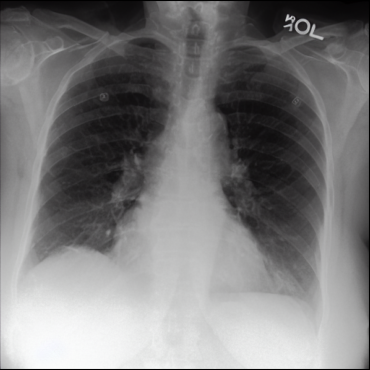

Figure 2: Fusion process applied to an image from the tail class Tortuous Aorta (a.1) and one of its neighbor images from the head class Atelectasis (b.1). (a.2) and (b.2) are channelwise Maximum Intensity Projections of the sparse vectors obtained from (a.1) and (b.1) respectively. In (a.3) and (b.3), we use EigenCAM to find attention maps for each sparse vector and define binary masks (yellow is one and dark purple is zero) using τh=τl=0,4formulae-sequencesubscript𝜏subscript𝜏𝑙04\tau_{h}=\tau_{l}=0,4 as thresholds. We combine the masked sparse vectors into (c) and decode the vector into a fused image (d). Finally, we apply five inference steps in (e) to obtain a less noisy image.

The method was tested by generating tail classes of a sampled version of MIMIC-CXR-LT 2023 [16, 13], a multilabel multiclass long-tailed dataset of chest X-rays. Our reduced sample version has only five head classes and five tail classes.